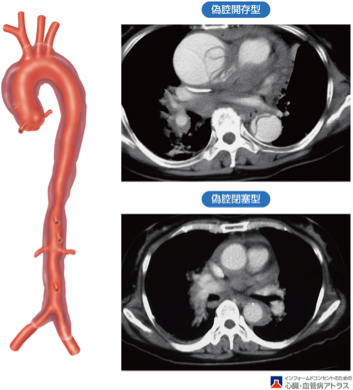

大動脈壁に裂け目が入り、壁が2枚に分かれてしまう病気で、元々の血液の通り道(真腔)に加えて新しく通り道(偽腔)ができてしまいます。

心臓から遠い大動脈しか裂けていないとき(B型)は血圧を厳重に管理する治療【降圧保存療法】となります。しかし、腹痛や下肢痛などの症状があるときは緊急手術【ステントグラフト内挿術】が必要です